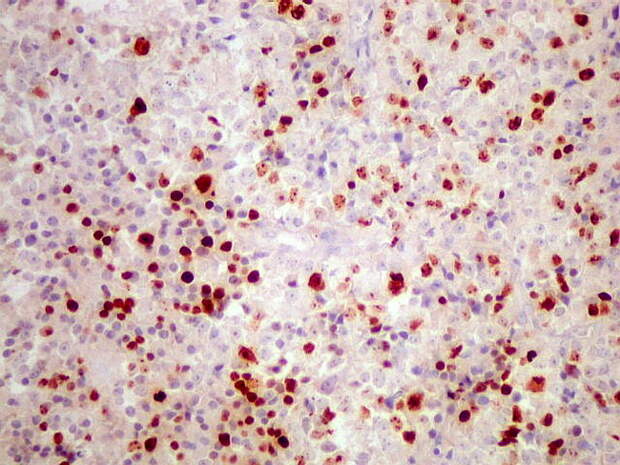

Микрофотографии гистологии глиобластомы головного мозга